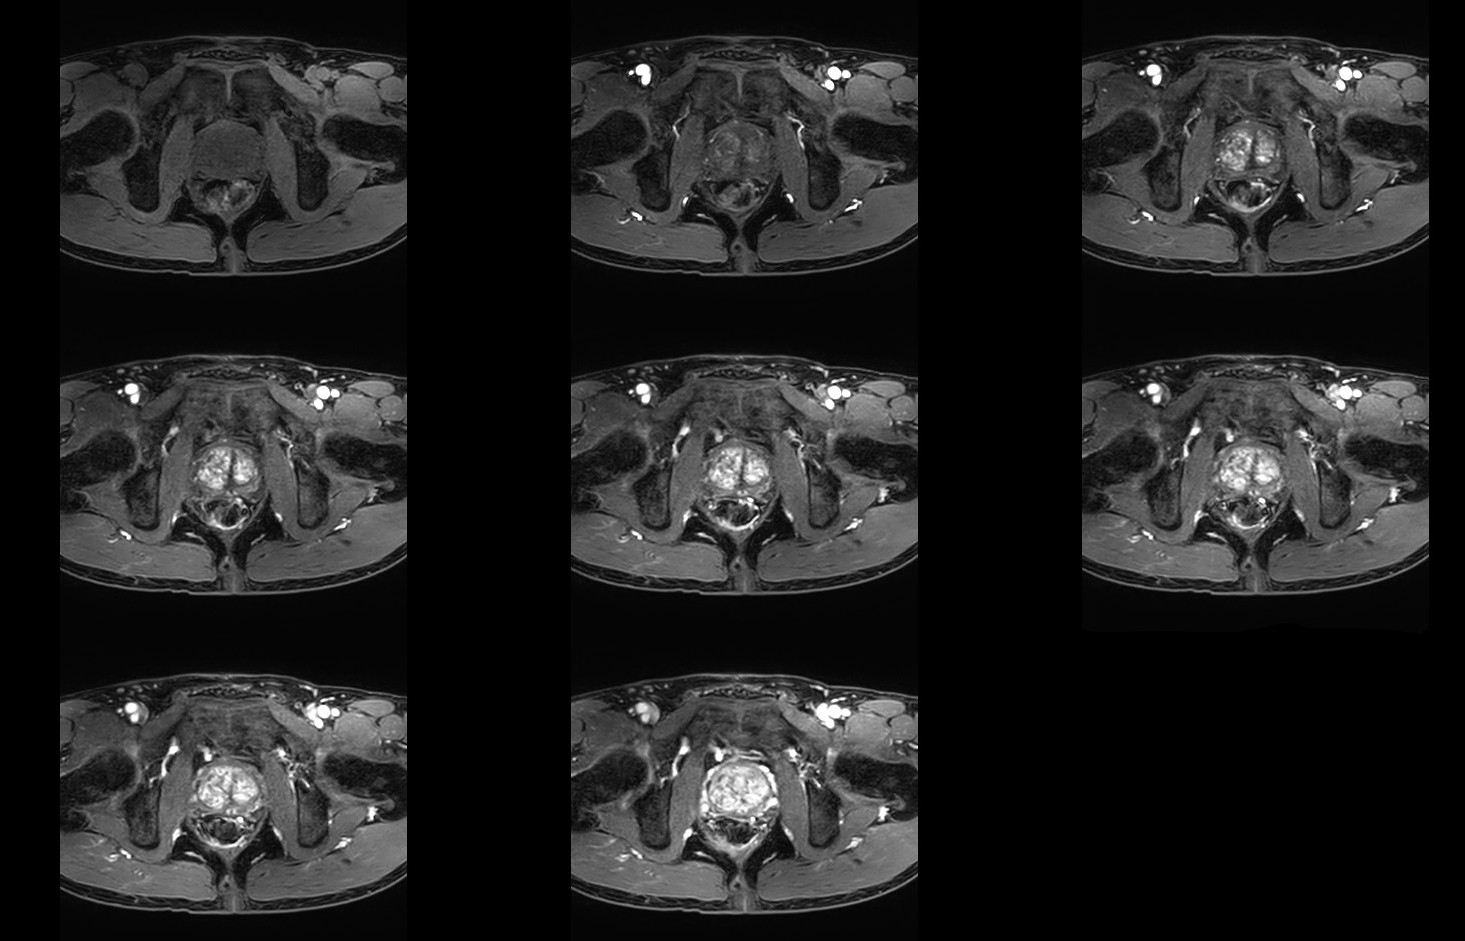

Fast Prostate imaging with SmartSpeed Precise

Kumamoto Chuo Hospital Japan

Used Solution